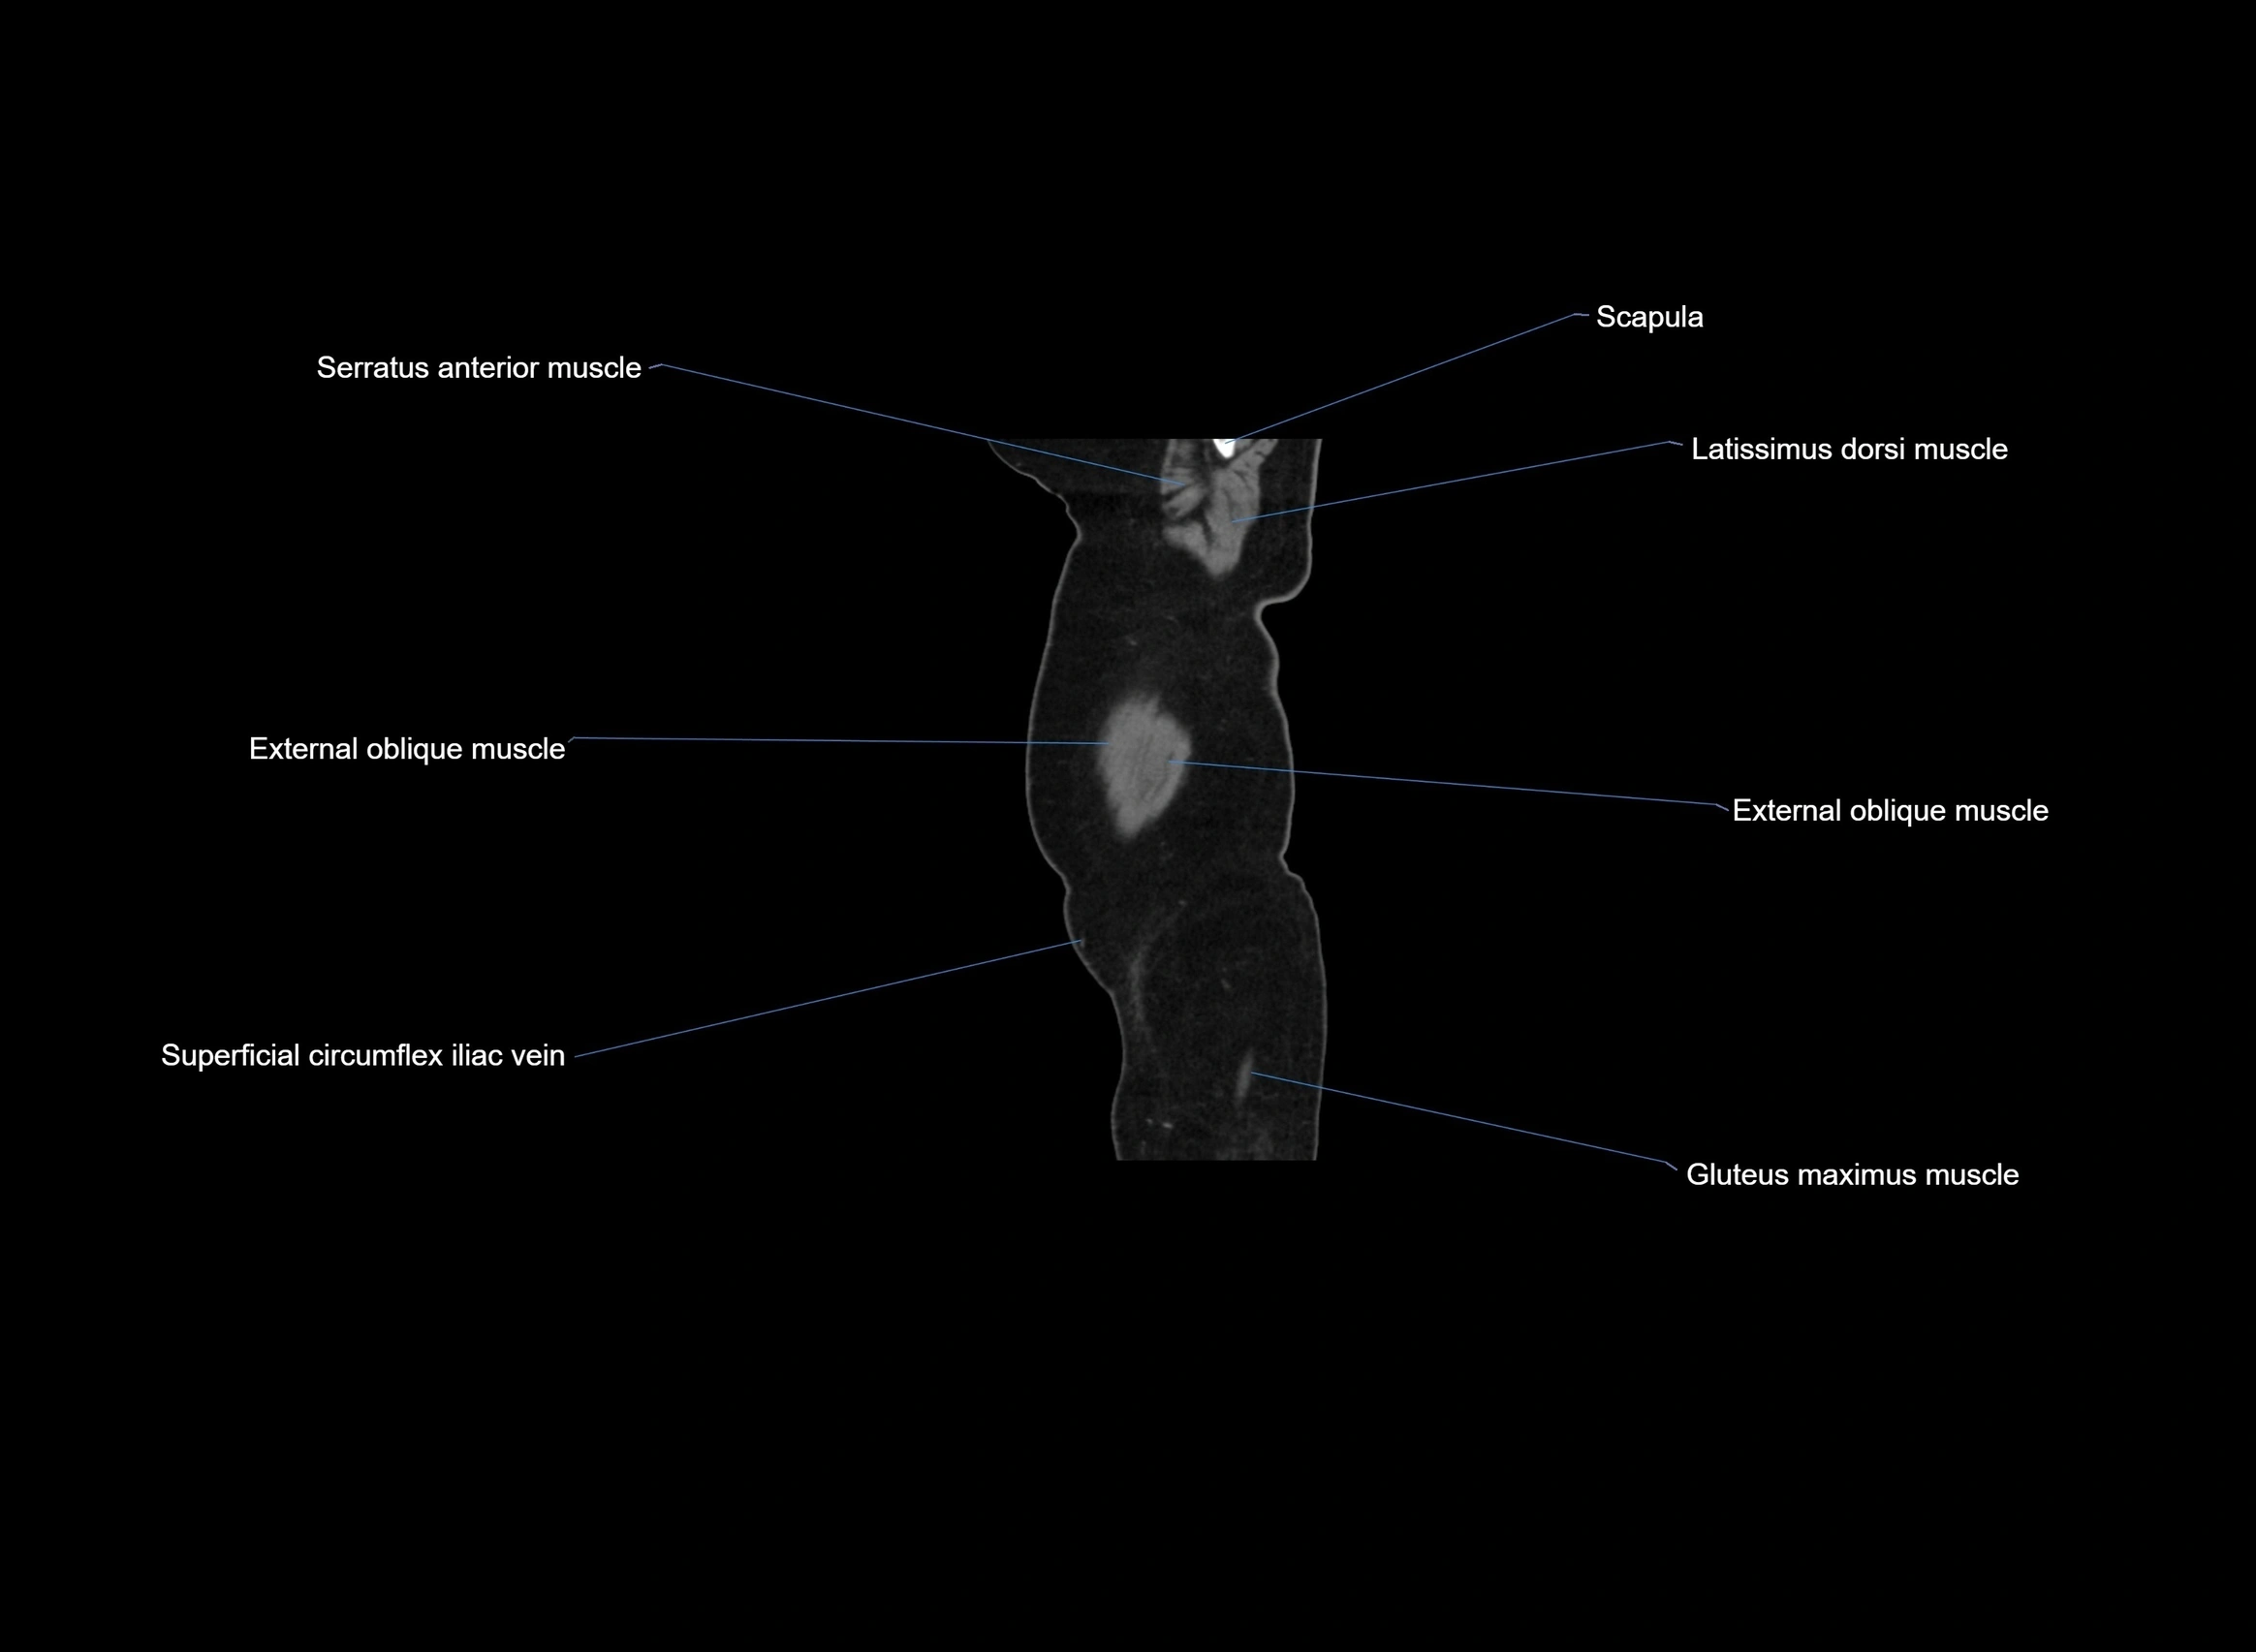

CT images